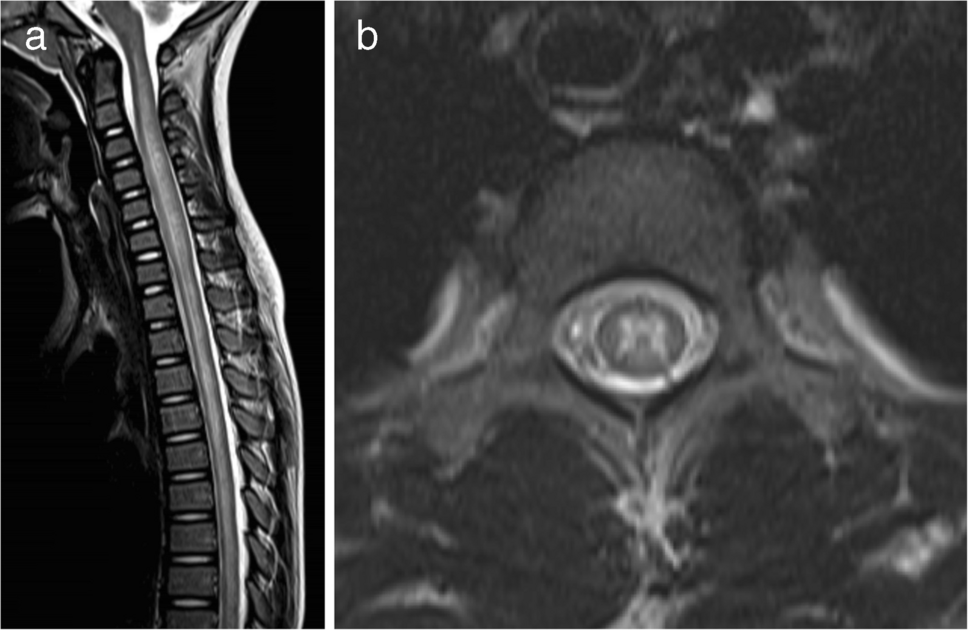

For patients with the ADEM phenotype, the mean widespread score was 2.7 (median 2, range 1–5). In seven cases, only multifocal supratentorial white matter lesions were observed, corresponding to a widespread score of 1. Spinal MRI was performed in 22 of the 39 patients (56%), and myelitis was identified in 10 of these 22 patients (45%). Except for one patient, nine cases showed longitudinally extensive lesions involving the central gray matter on axial images (Fig. 3). Conus involvement was identified in two out of the nine patients; in one patient, evaluation of the conus was not possible due to incomplete MRI coverage. A summary of the MRI distribution of affected regions in MOGAD patients with the ADEM phenotype is shown in Table 2. Typical ADEM patterns (Fig. 1) were observed in 15 of 39 patients (38%), whereas the remaining 24 patients (62%) exhibited at least one atypical feature for ADEM (Fig. 2). Among these 24 cases, 10 (42%) had one atypical feature, nine (38%) had two atypical features, and five (21%) presented with three atypical features. The most frequently observed atypical finding was the predominance of subcortical white matter lesions (17 of 39 patients, 44%), followed by the presence of small lesions (12 of 39 patients, 31%). Ten patients (26%) had both small and predominantly subcortical white matter lesions. These findings were compared with those reported by Baumann et al. [24], as summarized in Table 3.

Fig. 3

Magnetic resonance images illustrate myelitis in myelin oligodendrocyte glycoprotein antibody-associated acute disseminated encephalomyelitis in a 6-year-old girl. a Sagittal T2-weighted image shows a longitudinally extensive spinal cord lesion. b Axial T2-weighted image at the upper thoracic level reveals a hyperintense lesion involving the central gray matter (H-sign)